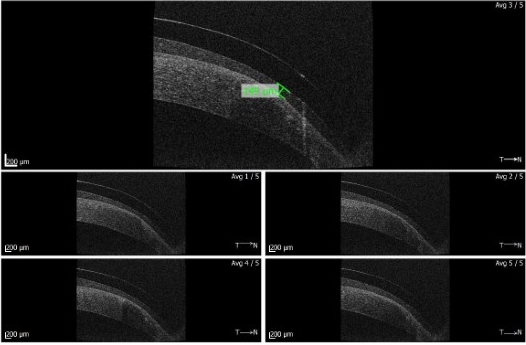

Fig 2. Anterior OCT of the lens at the nasal graft/host junction

Over the past 18 months, Watters has fit a number of patients within his practice with the help of Rose. Patients included several with extreme proud grafts and several with distorted post-radial keratometry (RK) cases, which were all quite different geometries to each other, he said, and all of whom were struggling with existing custom lens modalities. Case DC, for example, was a 54-year-old web designer with a proud graft and an unsuccessful rigid gas permeable wearer (Fig 1). Attempts had been made to refit him with a standard (prolate) semi-scleral lens and then a hybrid, with limited success, said Watters. “But with the ability to tuck in the mid-periphery (Fig 2) over the host-graft junction with this new oblate design, we achieved a stable and much more comfortable fit – he was a very happy camper!”